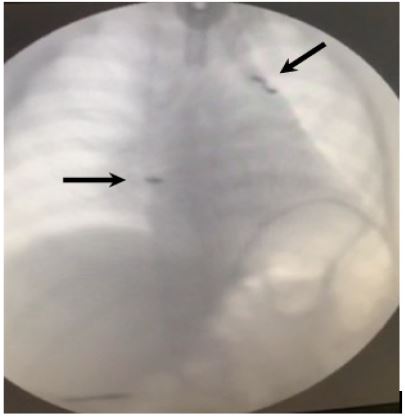

Figure 3: Postoperative chest radiograph. Pacemakers pointed by arrows.

For the present time, child breathing spontaneously (Figure 3), do not require respiratory support, and physically does not differ from peers.

Right diaphragm was elevated on the level of III rib and left – on the level of V rib with the asynchronized movements on a fluoroscopic examination (12.09.2020).

Plain chest radiography/fluoroscopy and ultrasonography are the gold standard for confirmation of paresis/paralysis of diaphragm [5,17]. Diaphragmatic asymmetry is not present in bilateral diaphragmatic paralysis [9], however, in our case both hemidiaphragms were elevated with more prominent elevation on right side.